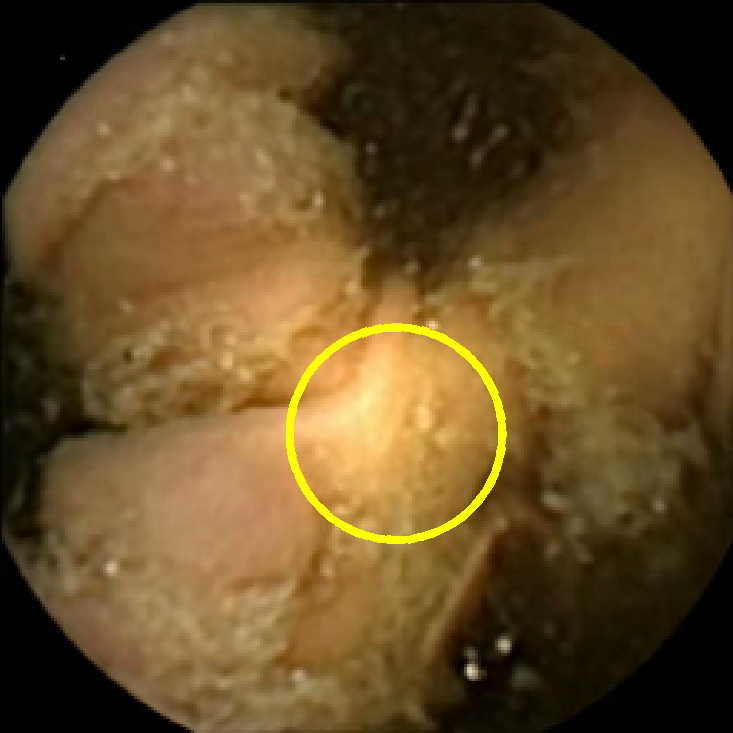

In Figure 5 we show the circles of radius corresponding to the features that were correctly classified as polyps by (29). We observe that the classifier was able to identify the polyps of a variety of shapes even in the presence of small amounts of trash liquid (first row) or when the polyps are located next to mucosal folds (rows two to four in column (c)).